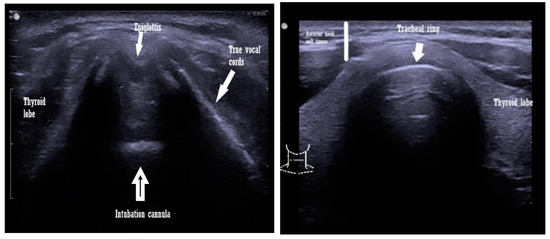

The transcutaneous approach comprises the trans laryngeal and transtracheal ultrasound windows used to evaluate the upper airway and can be performed using either a low- or a high-frequency transducer. The orientation of the probes can be one of the following: sagittal, parasagittal, oblique, or transverse [12,13,14] (Scheme 1).

Scheme 1.

Transcutaneous view with a linear ultrasound probe of an intubated patient airway (left image) and a non intubated patient (right image).

The subglottic view of the trachea can offer a proper measurement for choosing the correct cannula, simple or double lumen to avoid over - instrumentation of the airway. The trachea appears on the ultrasound as a curvilinear structure, hyperechoic, with artifacts such as comet tail and shadowing [31]. The diameter measured to determine the proper cannula size is the subglottic airway one and for the double lumen tube is the measurement of tracheal width at the suprasternal notch level [32,33] (Scheme 1).